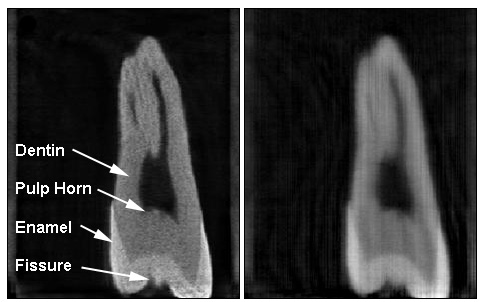

Figure 1. Tomographic reconstruction of a third mandibular molar from only 23 views. Left, with Liao’s algorithm. Right, with an Algebraic Reconstruction Technique, widely used in commercial scanners. Data from Maaria Rantala of PaloDEx Group.

In 2006, IMA postdoc Hstau Y. Liao invented a new reconstruction algorithm which produces high resolution 3-dimensional images even when the number of projections are small. Early tests on dental data provided by the University of Minnesota School of Dentistry have been very promising. The University of Minnesota is pursuing a patent on the technology Liao created. In the mean time, a major global medical imaging company is assessing Liao’s invention for possible licensing.